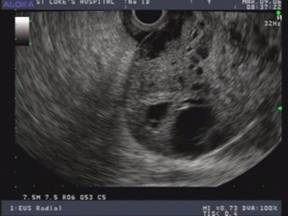

The EUS appearance of mucinous cystic neoplasm is variable. They are commonly associated with a visible wall and septations of variable thickness, and peripheral calcifications can be seen in some cases (Figures 1 and 2) [43]. Invasive malignancy has been associated with the presence of thick or irregular cyst wall, intramural nodules or solid components and larger cyst size (Figure 3) [14]. EUS-FNA cytology could reveal columnar epithelial cells in up to half of the patients in association with extracellular mucin [34, 46]. Mucin is frequently identified on EUS-FNA of mucinous cystic neoplasm and cyst fluid is typically clear with elevated CEA levels and low amylase. Mucinous cystic neoplasms are premalignant lesions but the risk of malignant degeneration is likely less than that of IPMN [45]. The risk of malignancy in these tumors described in a series of 163 patients was found to be 17.5% [47]. Therefore, surgical resection is recommended for all surgically fit patients. The prognosis after surgery for mucinous cystic neoplasm that have not undergone malignant transformation is excellent and the 5-year survival for mucinous cystadenocarcinomas post resection exceeds 60% [6, 48].

Figure 3. EUS findings in a middle age female patient with a mucinous cystic neoplasm in the body of the pancreas. A thick wall and a solid mass are features suggestive of malignancy. Surgical resection confirmed mucinous cystadenocarcinomas. |